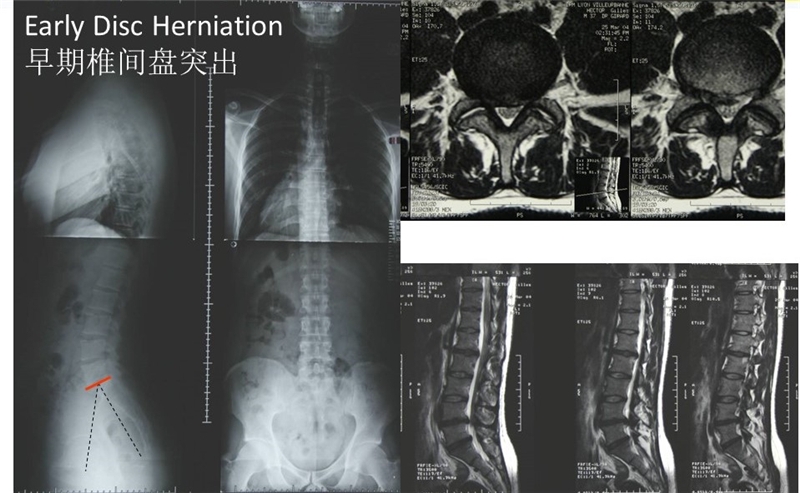

在腰椎前凸较小的1型和2型人群中,腰椎接触应力主要集中于前柱和中柱,此类人群更易出现早期椎间盘退变;而在腰椎前凸较大的4型人群中,腰椎应力主要集中于后柱,此类人群腰椎小关节和峡部应力负荷较大,易出现小关节增生、腰椎滑脱和侧方滑移。

1型脊柱较早发生椎间盘退变